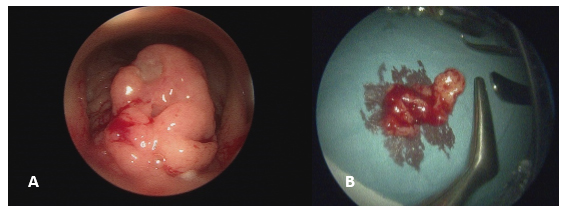

A 22-year-old healthy woman presented to the Emergency Department with a 6-month history of nasal congestion and left-sided otorrhea. Otomicroscopy of the left ear showed a polyp in the external auditory canal blocking direct visualization of the tympanic membrane. In-office nasolaryngoscopy showed left-sided polypoidal swelling in the Post-Nasal Space (PNS). No cervical lymph nodes were palpable on neck exam. She was treated with oral and topical antibiotics and encouraged to use a nasal rinse and decongestant. Magnetic Resonance Imaging (MRI) of the left middle ear ruled-out cholesteatoma but did identify a lesion in the deep parotid gland suspicious for necrosis and abnormal tissue in the nasopharynx which was biopsied. Histology confirmed multiple non-caseating granulomas suggestive of sarcoidosis. Given the absence of information in the literature on how to treat nasopharyngeal sarcoidosis, it was decided to ablate the PNS lesion using cautery and further biopsies were sent to out-rule lymphoma and re-test for Mycobacterium Tuberculosis (TB) (Figure1). The biopsies were culture-positive for Mycobacterium Tuberculosis complex despite not displaying respiratory symptoms. Chest x-ray and Computed Tomography scan (CT) of the thorax ruled out pulmonary TB. This could have resulted in aerosolization of the mycobacterium, but surgical staff had negative QuantiFERON Tests possibly because all were wearing FFP2 masks, customary during the COVID-19 pandemic. She was commenced on the standard four drug Anti-TB treatment for 6-months and the public health team was informed.

Figure 1: Intra-operative images of the post-nasal space polypoid mass pre and post excision. A) Zero degrees nasoendoscopy showing a large polypoid mass in the left post-nasal space. B) Suction adenoidectomy was performed, and samples were sent for both histology and TB culture.